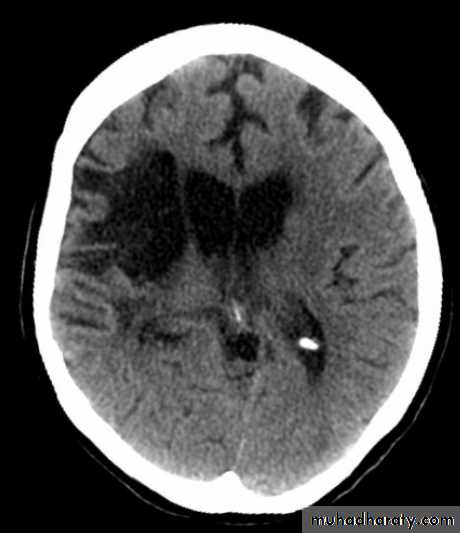

Acute Intra cerebral hematoma

CT finding :Hyper dense area , surrounded by edema , any where within the brain parenchyma.

Shifting of the midline

Compression of the ipsi lateral ventricle .

Associated with infarction , # , trauma concussion , tumor …..

Hypertensive Hemorrhage